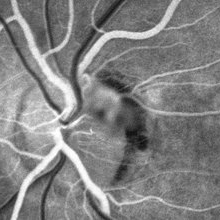

VHL "Free Floating" Juxtapapillary Hemangioblastoma

Jul 1 2014 by John S. King, MD

30-year-old female with fhx VHL and CNS hemangioblastomas and visceral lesions. P/C with a floater (no PVD or VH) after episodes of vomiting.

Photographer: Wayne A Ladlee Jr

Imaging device: FA 26 sec

Condition/keywords: retinal hemangioblastoma, Von Hippel-Lindau